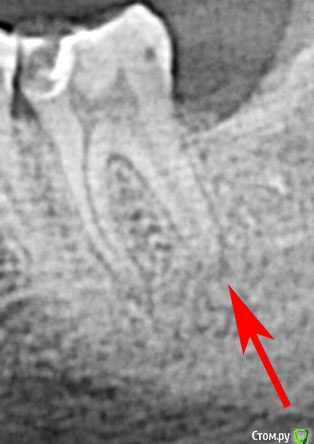

DmitrySH Опубликовано 15 июня, 2017 Поделиться Опубликовано 15 июня, 2017 На снимке связка зуба расширена, что свидетельствует о наличии воспаления. Убирайте нерв. Еще надо обратить внимание на верхние седьмые. На снимке все неоднозначно. Лучше сделать КТ Ссылка на комментарий

pogoreliy Опубликовано 15 июня, 2017 Автор Поделиться Опубликовано 15 июня, 2017 (изменено) На снимке связка зуба расширена, что свидетельствует о наличии воспаления. Убирайте нерв. А откуда оно там вообще могло взяться? Все ощущения от него? Вы про это? Изменено 15 июня, 2017 пользователем pogoreliy Ссылка на комментарий

DmitrySH Опубликовано 15 июня, 2017 Поделиться Опубликовано 15 июня, 2017 А откуда оно там вообще могло взяться? Все ощущения от него? Вы про это?Взялось от поражения пульпы Ссылка на комментарий

pogoreliy Опубликовано 15 июня, 2017 Автор Поделиться Опубликовано 15 июня, 2017 (изменено) А как нижний кусок зуба умудрился воспалиться от поражения пульпы наверху? или я что-то снова не понял? Изменено 15 июня, 2017 пользователем pogoreliy Ссылка на комментарий

dok1 Опубликовано 16 июня, 2017 Поделиться Опубликовано 16 июня, 2017 Запарился. Принял вас за стоматолога. Теперь как с пациентом - кариозная полость, это входные ворота для инфекции. Она прошла по каналу до верхушки. Дальний канал широкий с более толстым сосудом, и ответная реакция организма более быстрая. Пройдя по корню, инфекция попала в кость челюсти и та самая кость начала растворяться от воспаления. Пока вы нам пытаетесь что-то доказать, ситуация только ухудшается. 2 Ссылка на комментарий